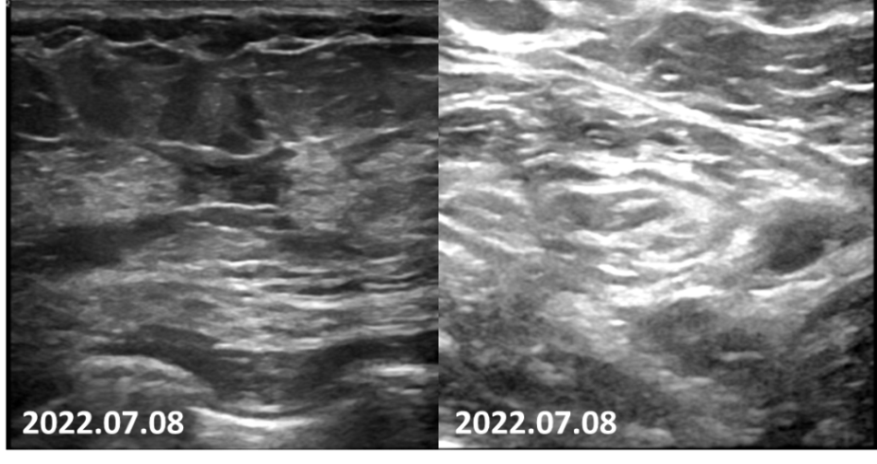

疗效评估:2疗程后,患者肿瘤明显减小,PR。

2022-07-08乳腺MRI报告:左乳上方象限病变可见明显强化,边界不清,大小约24mm×30mm×21mm(上下径×左右径×前后径),病变前缘距乳头约34mm,后缘距离胸壁约11mm。右乳约11点钟方向病变可见明显强化,边界不清,直径约9mm,病变前缘距乳头约50mm,后缘距离胸壁约32mm。左侧腋窝淋巴结肿大,最大直径约8mm。

图4.2疗程后患者左侧乳房肿物退缩明显,强化程度减低。

2022-07-08乳腺超声:左乳可见多处低回声结节,较大者位于12~1点钟,大小约20.6mm×6mm×18.3mm,距体表12mm,距乳头26mm,形态不规则,边缘成角,内回声不均匀,CDFI:内可及点状血流信号。左侧腋窝可见数个淋巴结回声,髓质消失,较大者大小约18mm×8mm,CDFI:内可见点状血流信号。右侧腋窝及双侧锁骨上窝未见明显肿大淋巴结。

图5.2疗程后可见患者左侧乳房肿物仅余核心部分,左腋窝淋巴结形态已接近正常。